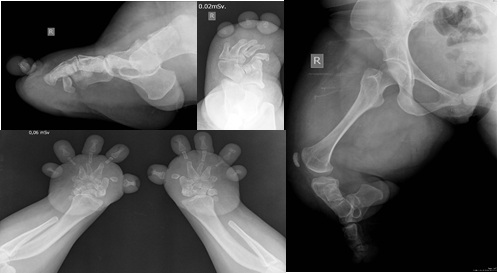

La condrodisplasia de Grebe es un trastorno raro autosómico recesivo que pertenece al grupo de las osteocondrodisplasias. Clínicamente se caracteriza por un severo dismorfismo con una marcada micromelia y deformidad de las extremidades inferiores y superiores. Conocer este tipo de síndrome orienta a dar mejores diagnósticos y permite el diagnóstico diferencial con patologías más comunes, como la acondroplasia. Se presenta una paciente de 35 años con diagnóstico de síndrome de Grebe desde los 10 años. El síndrome de Grebe tiene una muy baja incidencia; por este motivo, es poco conocido por el cuerpo médico en general y aun menos para los ortopedistas, quienes serán los encargados de tratar a estos pacientes. AbstractGrebe syndrome is a rare autosomal recessive disorder that belongs to the group of osteochondrodysplasias. Clinically, it is characterized by severe dysmorphism, marked micromelia and deformities of the lower and upper limbs. Recognition of this syndrome allows to give better diagnoses and to establish a differential diagnosis with more common pathologies, such as achondroplasia. We present a 35-year-old woman with diagnosis of Grebe syndrome at the age of 10. Grebe syndrome has a very low incidence; therefore, it is unknown by general physicians and still less by orthopedic surgeons, who will treat these patients.Descargas